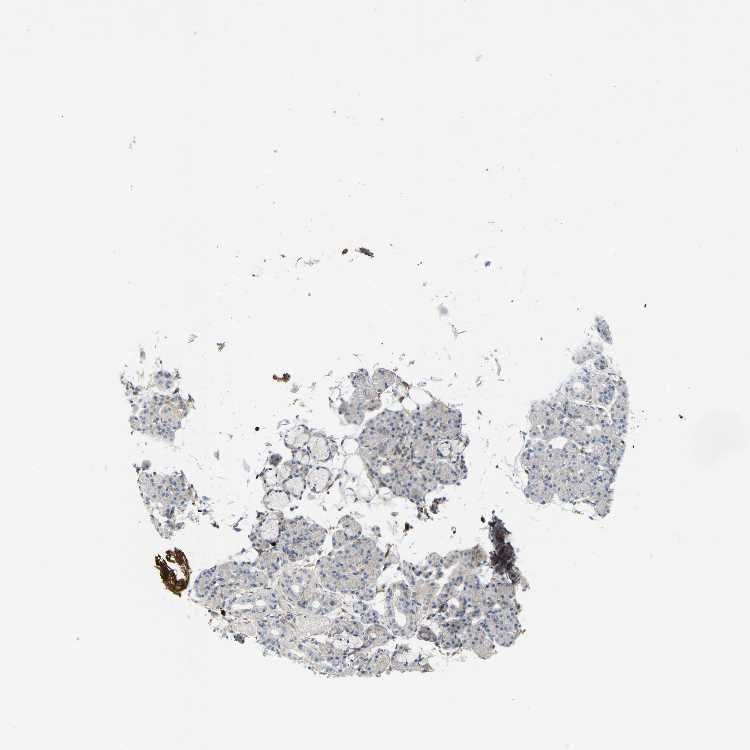

SALIVARY GLAND - Antibody stainingi

Antibody staining in the annotated cell types in the current human tissue is reported as not detected, low, medium, or high, based on conventional immunohistochemistry profiling in selected tissues. This score is based on the combination of the staining intensity and fraction of stained cells.

Each image is clickable and will lead to virtual microscopy that enables deeper exploration of all samples and also displays staining intensity scores, fraction scores and subcellular localization as well as patient and tissue information for each sample.

Antibody HPA019053Antibody HPA019061

Glandular cells MediumNot detected